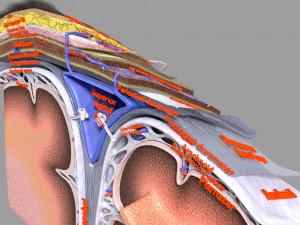

A blend model of brain along with its covering layers (meninges), skull bone and scalp labelled in detail and anatomically precise. The parts depicted are white, gray, pia, arachnoid, dura, bone, skin, fat, aponeurosis, periosteum, falx cerebri and more.

The material is high resolution image textures and normal maps based on non overlapping UVs. The texture and normal maps are packed with the blend file itself.